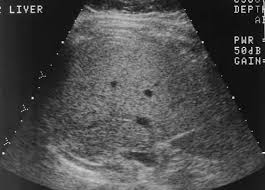

Fatty Liver Infiltration